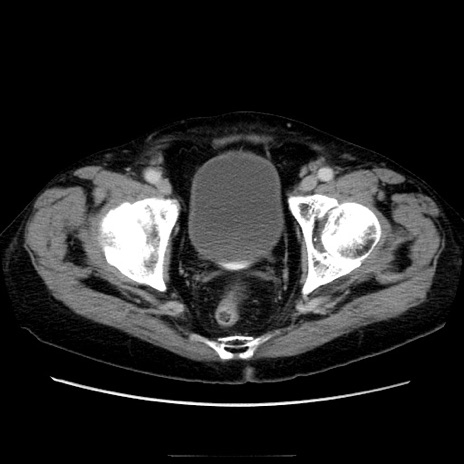

症例21(横断像)

【症例】70歳代男性

【主訴】腹痛

【現病歴】肝硬変・肝細胞癌にてかかりつけの方。約9時間前に食後より腹痛出現。症状が徐々に増悪し、嘔吐出現したため来院。

【既往歴】肝硬変、肝細胞癌(RFA、TACE後)

【身体所見】意識清明、表情苦悶様、BT 36℃、BP 129/78mmHg、P 88bpm、SpO2 97%(RA)、右上腹部から心窩部にかけて圧痛あり、反跳痛なし、筋性防御あり。

【データ】WBC 5800、CRP 0.16